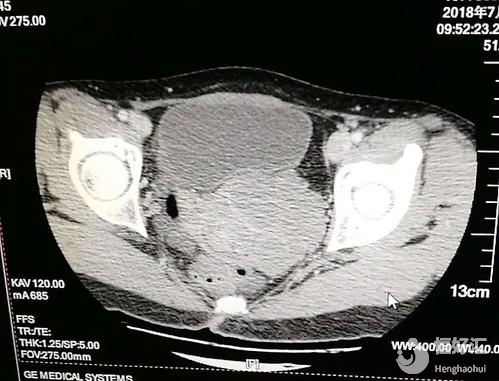

2、B超檢查:通過B超檢查可以清楚地顯示雙子宮和一側(cè)子宮積血宮頸擴張,對診斷也有很大的作用,同時還能提示一側(cè)腎臟的具體情況;

其實,如果對該疾病有充分的認(rèn)知,還有一定的了解,那么診斷并不困難。而診斷陰道斜隔最正確的方法就是B超檢查,根據(jù)B超檢查的精細(xì)準(zhǔn)確,可以提示雙子宮、雙宮頸和一側(cè)子宮頸的擴張積血,并且提示同側(cè)腎臟的缺如,對疾病確診也有很大的幫助。